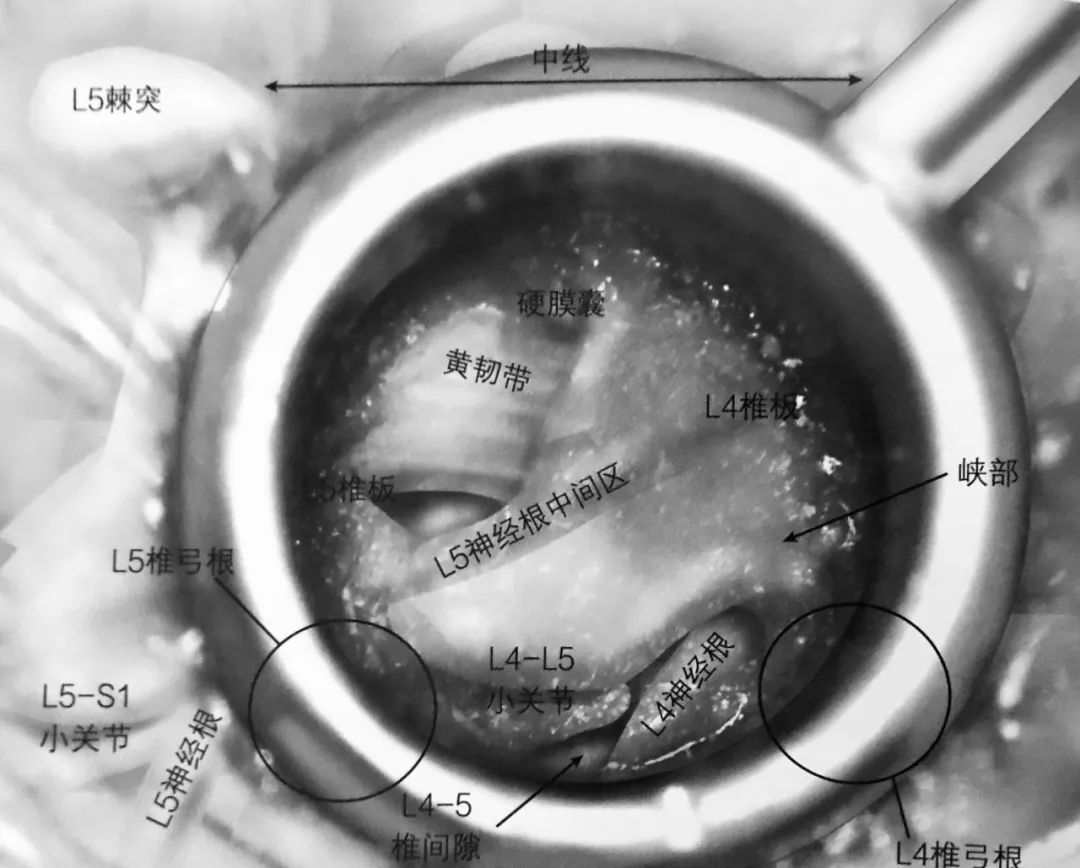

3. 一旦显露椎板,用高速磨钻磨除椎板,仅剩下黄韧带。椎板切除术要通过峡部延伸至外侧。取下的骨植入专门的收集袋中保存。

4. 椎板切除术向头端延至黄韧带止点,硬膜外脂肪或硬膜囊通常能看到。如图,椎板切除术切除范围的头端标志,磨钻用来切除外侧的峡部。

5. 一旦磨钻通过峡部,下关节突就可以去除,完成小关节切除术,显露病变椎间隙。

6. 切除黄韧带。最开始的时候要保留黄韧带,在实施减压时能起到保护硬膜囊的作用。

8. 一旦完成静脉丛电凝止血,下位的椎弓根(L5)及 L4-5 椎间隙就能看得很清楚。L5 神经根中间部就在椎弓根内缘。L4 神经根出口就在椎间隙上缘,但并不一定需要显露。